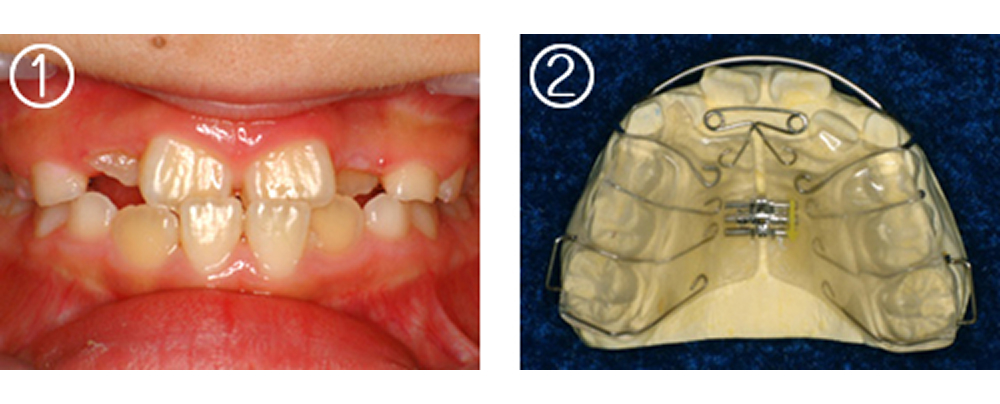

①術前:8歳 4前歯が反対咬合で歯が並ぶスペースも不足

②拡大床(エキスパンジョンスクリュー 床矯正装置)を作製

③装着した所

④4ヵ月後 反対咬合が改善し、歯が並ぶスペースも確保できた。ここまできていれば永久歯列になったときの矯正は簡単です